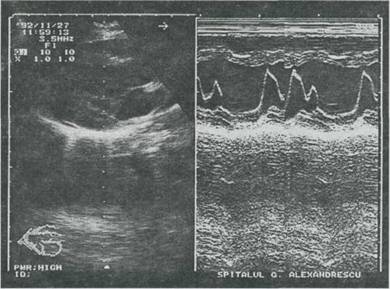

Radiografia cardiopulmonara este normala, iar pe traseul ECG se pot obiectiva tulburarile de ritm (mai precis cu metoda Holter). Echografic atât în modul M cât si bidimensional se obtin imagini sugestive. Aspectul "în hamac" pentru echografia unidimensionala si bombarea sistolica anormala, asimetrica în atriul stâng, mult deasupra inelului valvular, aspect comparat cu un "sombrero" evidentiat în sectiunea 4

Fig. 9-9. Prolaps teiesistoiic al valvei mitrale. Echocardiografie 2-D axul lung parasternai: cuspidul mitral flasc si alungit prolabeaza în cavitatea atriului stâng. Echograma mod M (dreapta imaginii) evidentiaza aspectul "în hamac" al ecoului mitral în sistola; este surprinsa o extrasistola.

cavitati a echografiei bidimensionale, constituie aspectele cele mai tipice.